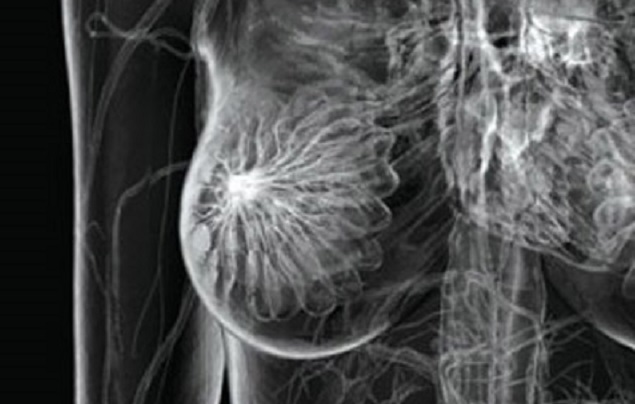

Il convegno ha l’intento di continuare il percorso di sensibilizzazione riguardo il tema del cancro al seno, affrontando questa problematica con la chiarezza e la sincerità che la medicina comporta, ma anche con la sensibilità ed il tatto che sono necessari per affrontare patologie come questa. Il tumore alla mammella, infatti, colpisce una donna su otto, con una proiezione di una su sei nei prossimi anni.